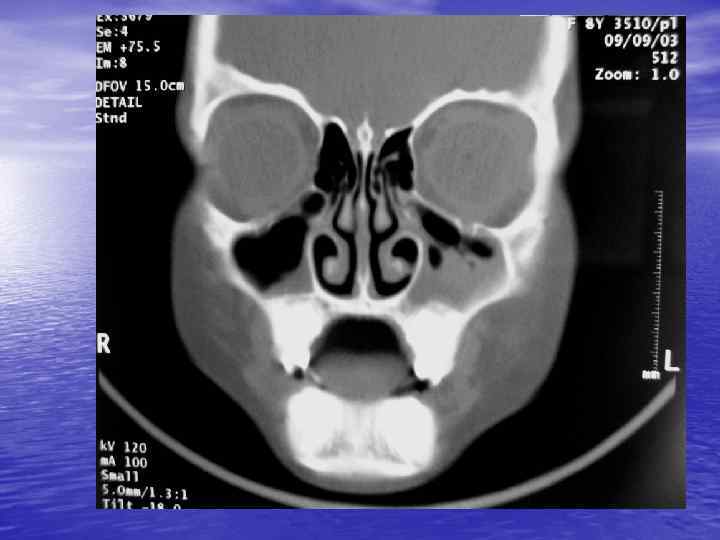

Структурный анализ Оценка основных макроскопических признаков: - положение - форма - размеры - характер контуров и структур патологически измененных участков

Структурный анализ

Денситометрический анализ Определение основных видов патологических образований: - обызвествленных - мягкотканных - жидкостных - жиросодержащих - воздухсодержащих